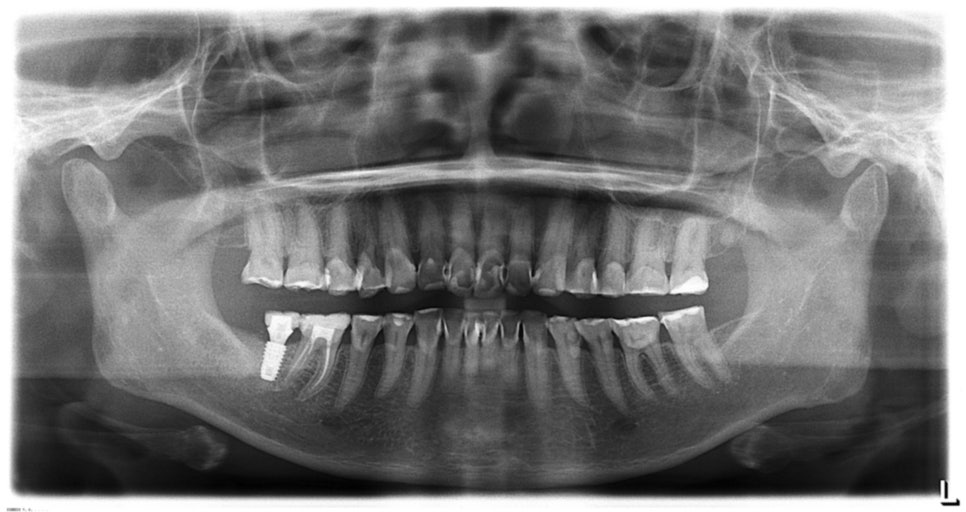

관리 전후 파노라마 사진을 보면 신경치료가 전혀 필요 없음을 확인할 수 있습니다. 일반적인 접근 방식인 '신경을 제거하고 크라운을 씌우는 방법'과는 다른 결과를 만들었습니다.

미니쉬 이후 파노라마 사진, 다발성 우식증이지만 다행스럽게도 신경치료는 없었습니다.